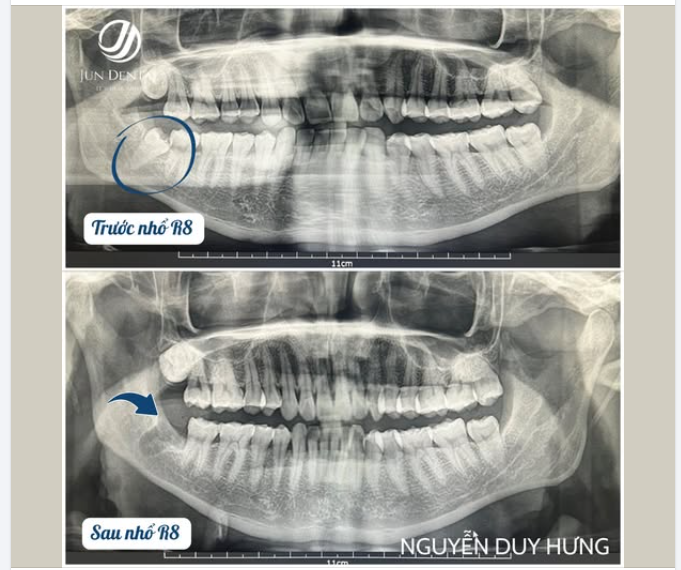

KHÁCH HÀNG NGUYỄN DUY HƯNG – NHỔ RĂNG KHÔN 48 NGHIÊNG NGẦM NHẸ NHÀNG, KHÔNG ĐAU TẠI JUNDENTAL